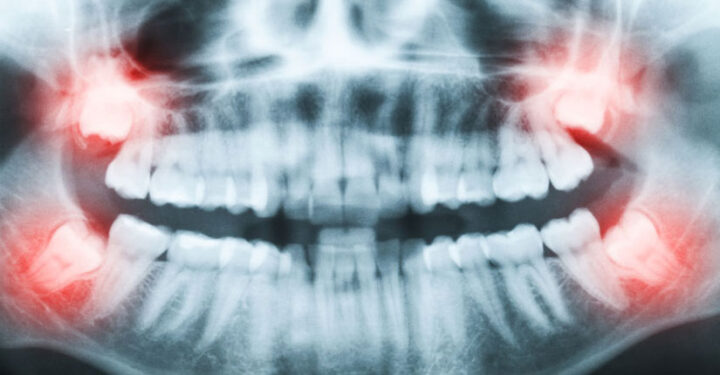

Dental Implants for Missing Teeth: Permanent, Natural-Looking Solutions Dental implants are the gold standard for replacing missing teeth, restoring both function and aesthetics with long-lasting results. As advanced tooth replacement solutions, dental implants provide exceptional stability for crowns, bridges, and implant-supported dentures—helping you regain a confident, natural-looking smile. Dental implants are small, biocompatible titanium posts…